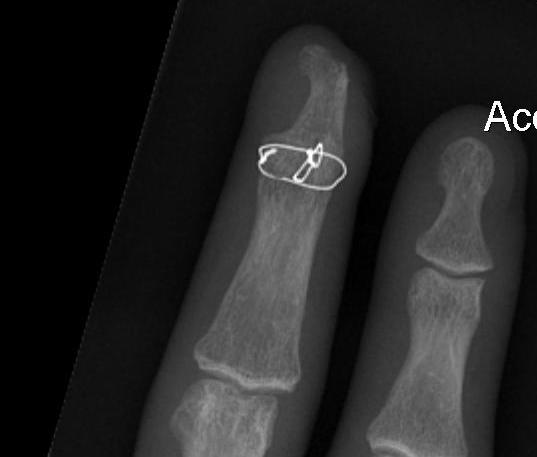

B. K wire and TBW

- single intra-axial K wire

- pass retrograde first, reduce, anterograde

- Circular wire

- small drill holes and pass 25 or 26 gauge wire

- tension